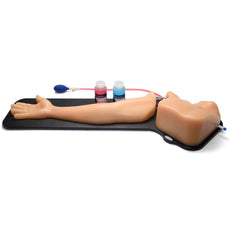

Frequently Bought Together

Replacement tissue insert for the Thoracentesis and Thoracostomy Ultrasound Training Model (BPTT1000-1).Choose from three options: